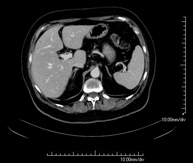

- TC Abdomen

Prueba diagnóstica que consiste en obtener imágenes del abdomen de alta definición anatómica (hígado, vesícula biliar, vía biliar, páncreas, bazo, estómago, intestinos, riñones, estructuras vasculares, vejiga, útero y ovarios, etc.) mediante el empleo de un equipo de TC (Tomografía Computarizada). Dichas imágenes se estudian posteriormente en una estación de trabajo que permite reconstrucciones bidimensionales en diferentes planos del espacio, y también reconstrucciones 3D (volumétricas). La mayoría de estudios requieren el empleo de contraste yodado para mejorar la definición de las imágenes.